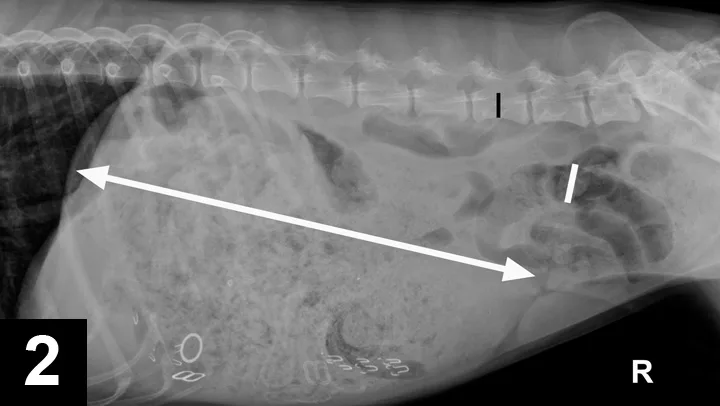

Abdominal Radiography: Right lateral (Figure 1A, above) and VD views (Figure 1B) of the abdomen were obtained.

Radiographic Findings: The right lateral view (Figure 2) showed severe gastric distension (white double headed arrow) with granular ingesta, intermediate opacity oval structures seen in the ventral stomach on the lateral view (suggesting rubber bands or hair elastics), and various metallic structures (compatible with bra straps and hooks). The small and large intestines are displaced caudally by the gastric distension. The gas-distended small intestine (white bar) measured up to 24 mm and the height of the L5 vertebral body (black bar) was 11 mm; this gives a small intestinal to L5 ratio of 2.2, which is much greater than the upper limit of 1.6 for normal small intestine to L5 height ratio.1